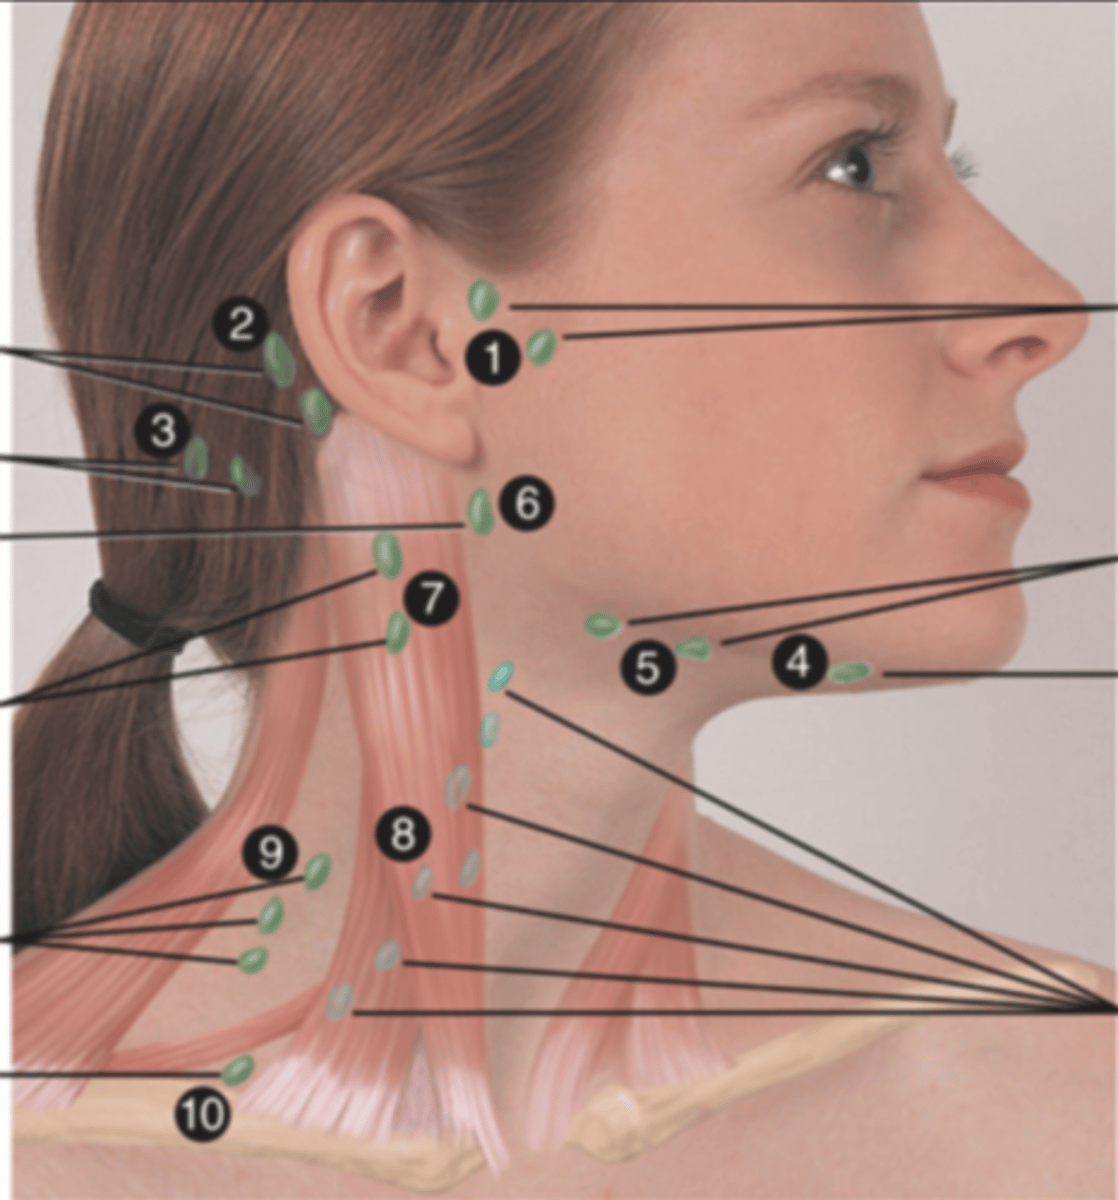

Major Lymph Nodes in the Neck (FUN!)

(Party People Often Sell Sardines Just So Dogs Pee Silver)

Preauricular Lymph Node

Lymph node in front of the ear (1)

Posterior Auricular Lymph Node

Lymph node behind the ear (2)

Occipital Lymph Node

Lymph node at the base of skull (3)

Submental Lymph Node

Lymph node under the chin (4)

Submandibular Lymph Node

Lymph node along base of mandible (5)

Jugulodigastric (Tonsil) Lymph Node

Lymph node under the angle of the mandible (6)

Superficial Cervical Lymph Node

Lymph node overlying the sternomastoid muscle (7); can feel enlarged even when there are no problems

Deep Cervical Chain Lymph Node

Lymph node located on the posterior triangle of the neck (8)

Posterior Cervical Lymph Node

Lymph node in the posterior triangle along the edge of the trapezius muscle (9)

Supraclavicular Lymph Node

Lymph node just above and behind the clavicle, at the sternomastoid muscle (10)